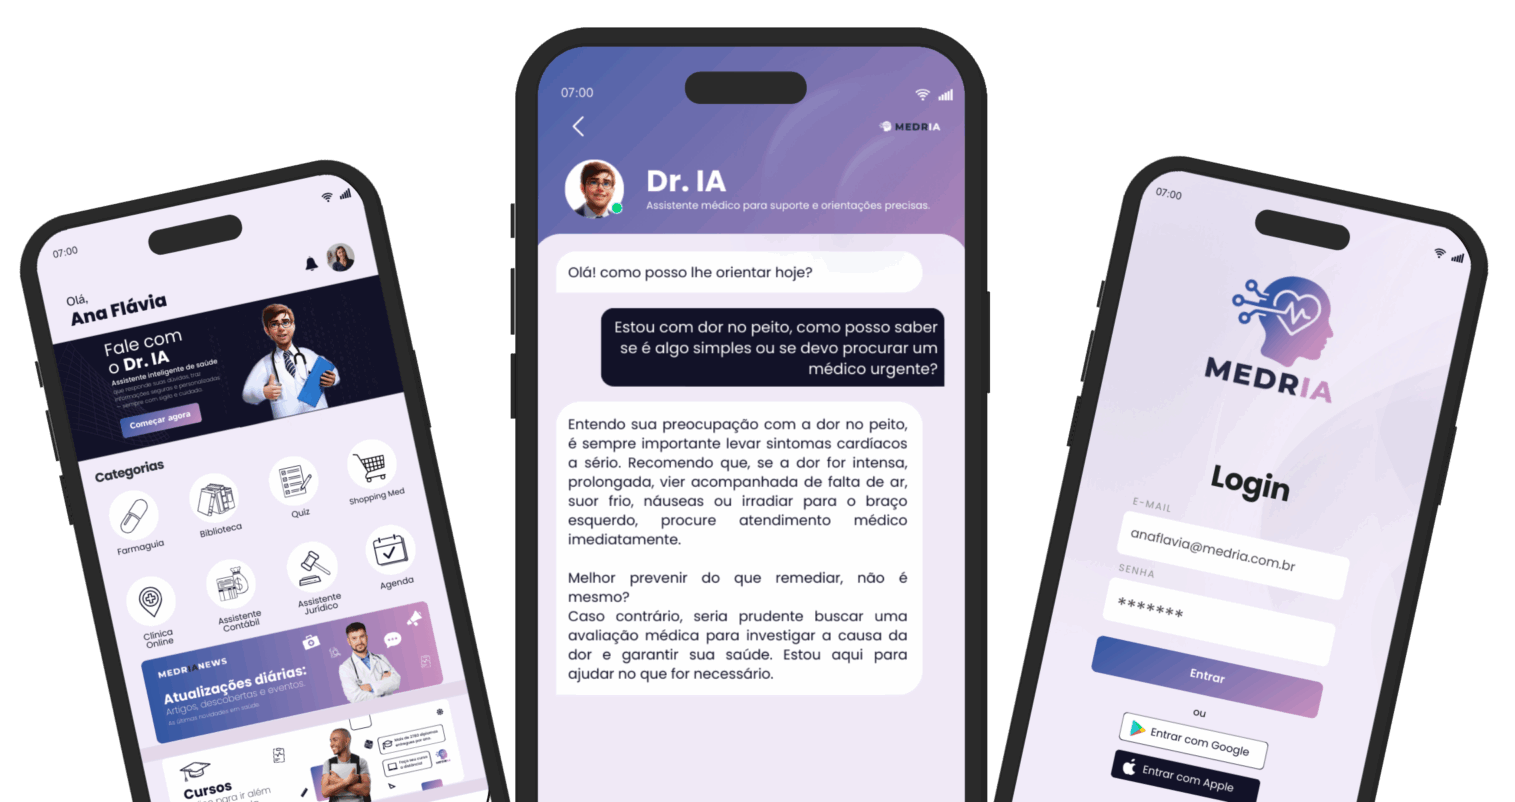

Recursos

Uma IA completa com soluções diferentes para cada necessidade.

Para profissionais da saúde e estudantes

Cursos e News

Atualização contínua com conteúdos médicos e novidades da área

Assistente contábil e jurídico

Suporte para sua carreira e rotina profissional

Assistente inteligente

Desenvolvido com base em uma biblioteca médica extensa e atualizada, feita para acompanhar os desafios reais da prática clínica.

Respostas clínicas em segundos, conteúdo técnico e confiável sempre disponível para te apoiar — um parceiro para decisões seguras.

Para o público em geral

Orientação confiável em saúde

Chat com assistente de saúde (IA), histórico e organização de informações pessoais além de dicas de autocuidado baseadas em evidências.

Clínica Online

Opinião médica confiável sem sair de casa

Quiz e biblioteca

Conteúdo simples para aprender e se cuidar melhor